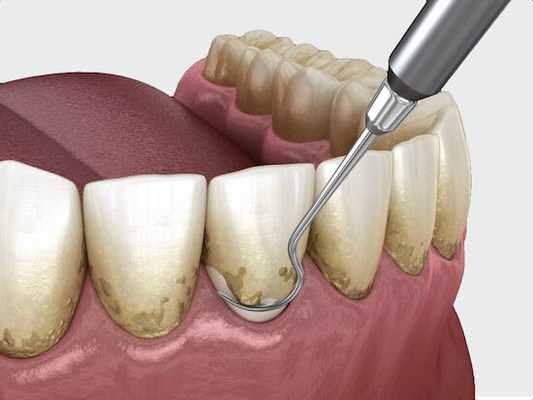

Чистка ультразвуком

Выполняется при помощи ультразвукового скалера. Процедура показана для удаления зубного камня.

Принцип чистки ультразвуком: в наконечник скалера вставляют насадку, совершающую ультразвуковые колебания. Одновременно с этим в нее подают струю воды. В момент соприкосновения насадки с отложениями, те удаляются с эмали. Благодаря эффекту кавитации (когда волны ультразвука распространяются в воде, образуя воздушные пузырьки), поверхность очищается от остального налёта.

Однако ультразвуковая чистка не удаляет мельчайшие частицы налёта, которые также необходимо устранить. Для этого применяется чистка Air Flow, профессиональное отбеливание или классическая полировка зубов щёткой и полировочной пастой.

Если не удалить остатки отложений, зубная поверхность останется шершавой, к ней быстро прилипнет новый налёт.